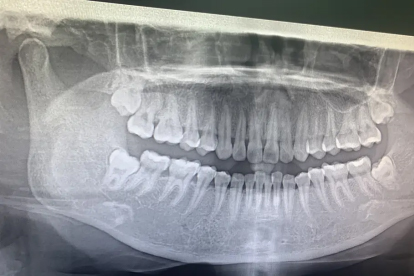

若智齿存在阻生或部分萌出,容易滞留食物残渣,引发智齿冠周炎反复发作,或导致邻牙蛀牙及牙根吸收,则建议拔除。这类智齿因位置不当,清洁困难,常成为细菌滋生的温床,不仅自身易发炎,还可能损害邻近健康牙齿。通过口腔X光片可明确智齿生长方向与邻近组织关系,为诊断提供依据。